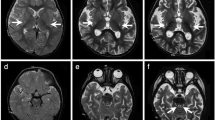

Here we present a male with LBSL in whom a novel DARS2 mutation was identified. At present, the patient is 27 years of age. He is the second child of healthy and non-consanguineous Japanese parents after an uneventful pregnancy and delivery. He has two healthy siblings. He started to walk at 1 year and 8 months. It was noted that he easily fell to the ground when he was 3.5 years. At that time, brain computed tomography was performed, and leukoencephalopathy was suggested. From the age of 4 years, he started to require support for walking. A walking aid and a wheelchair were needed from the age of 6 years and 10 years, respectively. Subsequently, nystagmus was noted at 13 years. His motor ability gradually deteriorated and he, at present, can use only his upper limbs. Intellectual ability has also declined. Routine laboratory examination, including metabolic screening and cerebrospinal fluid testing, showed no abnormalities involving lactic and pyruvate acids. Enzymatic analyses for arylsulfatase A and galactocerebrosidase were also normal. Brain magnetic resonance imaging examined at 27 years revealed white matter abnormalities in association with cystic findings (Figures 1a–d). The spinal cord was also involved. These findings were typical for LBSL. Although an elevation of lactate level was not clear by magnetic resonance spectroscopy at the same time (data not shown),4,5 such a pattern is not unusual. There are some LBSL patients who show normal lactate levels, which might occur due to advanced stage or a late onset of symptoms.6–8

Radiological findings and results of molecular analysis. (a–d) Axial magnetic resonance images examined at 27 years. T2-weighted axial images (a–c) and a fluid-attenuated inversion recovery image (d). (a) In the spinal cord, the posterior columns (yellow) and the lateral corticospinal tracts (red) are involved. (b) At the level of the pons, high signal intensity is shown in bilateral lesions in the pyramidal tracts (red), medial lemniscus (yellow), superior cerebellar peduncles (blue), and intraparenchymal trajectory of the trigeminal nerve (green). (c) At the level of the basal ganglia, the posterior limb of the internal capsule and periventricular white matter are affected. (d) High signal intensity is shown in the periventricular white matter associated with multiple small cysts. (e, f) Electropherograms of Sanger sequencing for the patient, his mother, and the sister. Although a c.228-20T>C polymorphism is shown in both the patient and his sister (e), c.228-15C>G is only present in the patient. c.358_359delinsTC (p.Gly120Ser) is commonly shown in all samples (f), and the affected amino acid is conserved among species (g).